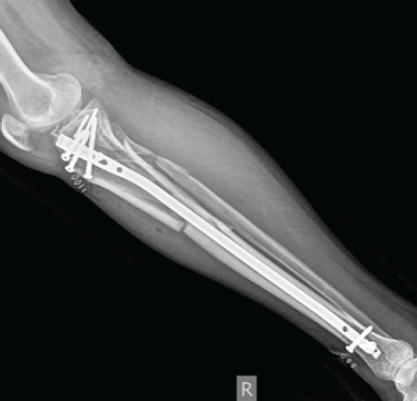

Figure 3: 6th month follow-up X-ray.